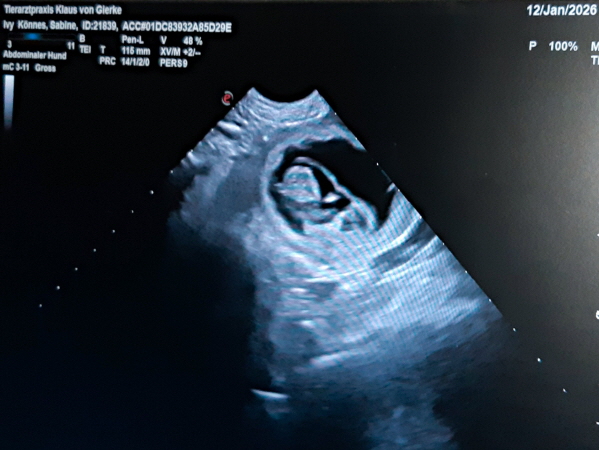

Uuups, unverhofft kommt oft. Ivy hatte sich in der Trächtigkeit gut entwickelt, die Ultraschalluntersuchung ließ 8-9 Welpen erkennen, alles ok. Sonntag, 08.02.2026: morgendlicher Alltag, Spaziergang mit den Dreien, noch 5 Tage bis zum errechnete Geburtstermin. Wieder zu Hause zeigte Ivy dunklen Ausfluss und die Alarmglocken erklangen. Also, ab zur Tierklinik, Ultraschall zur Überprüfung der Herztöne der Kleinen. Neben 7 (oder so) schlagenden Welpenherzen wurde auch ein verstorbener Welpe entdeckt. Da der Geburtskanal blockierte war, wurde kurz darauf ein Kaiserschnitt durchgeführt. Nach etwa 3 Stunden konnten wir dann Ivy, 9 lebende und einen verstorbenen Welpen abholen. Wie schön und wie schade ....